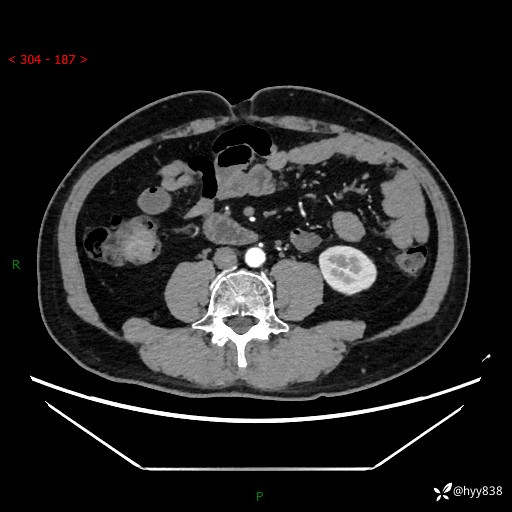

腹部CT增强扫描(外院CT平扫)

两期CT值:75hu 82hu